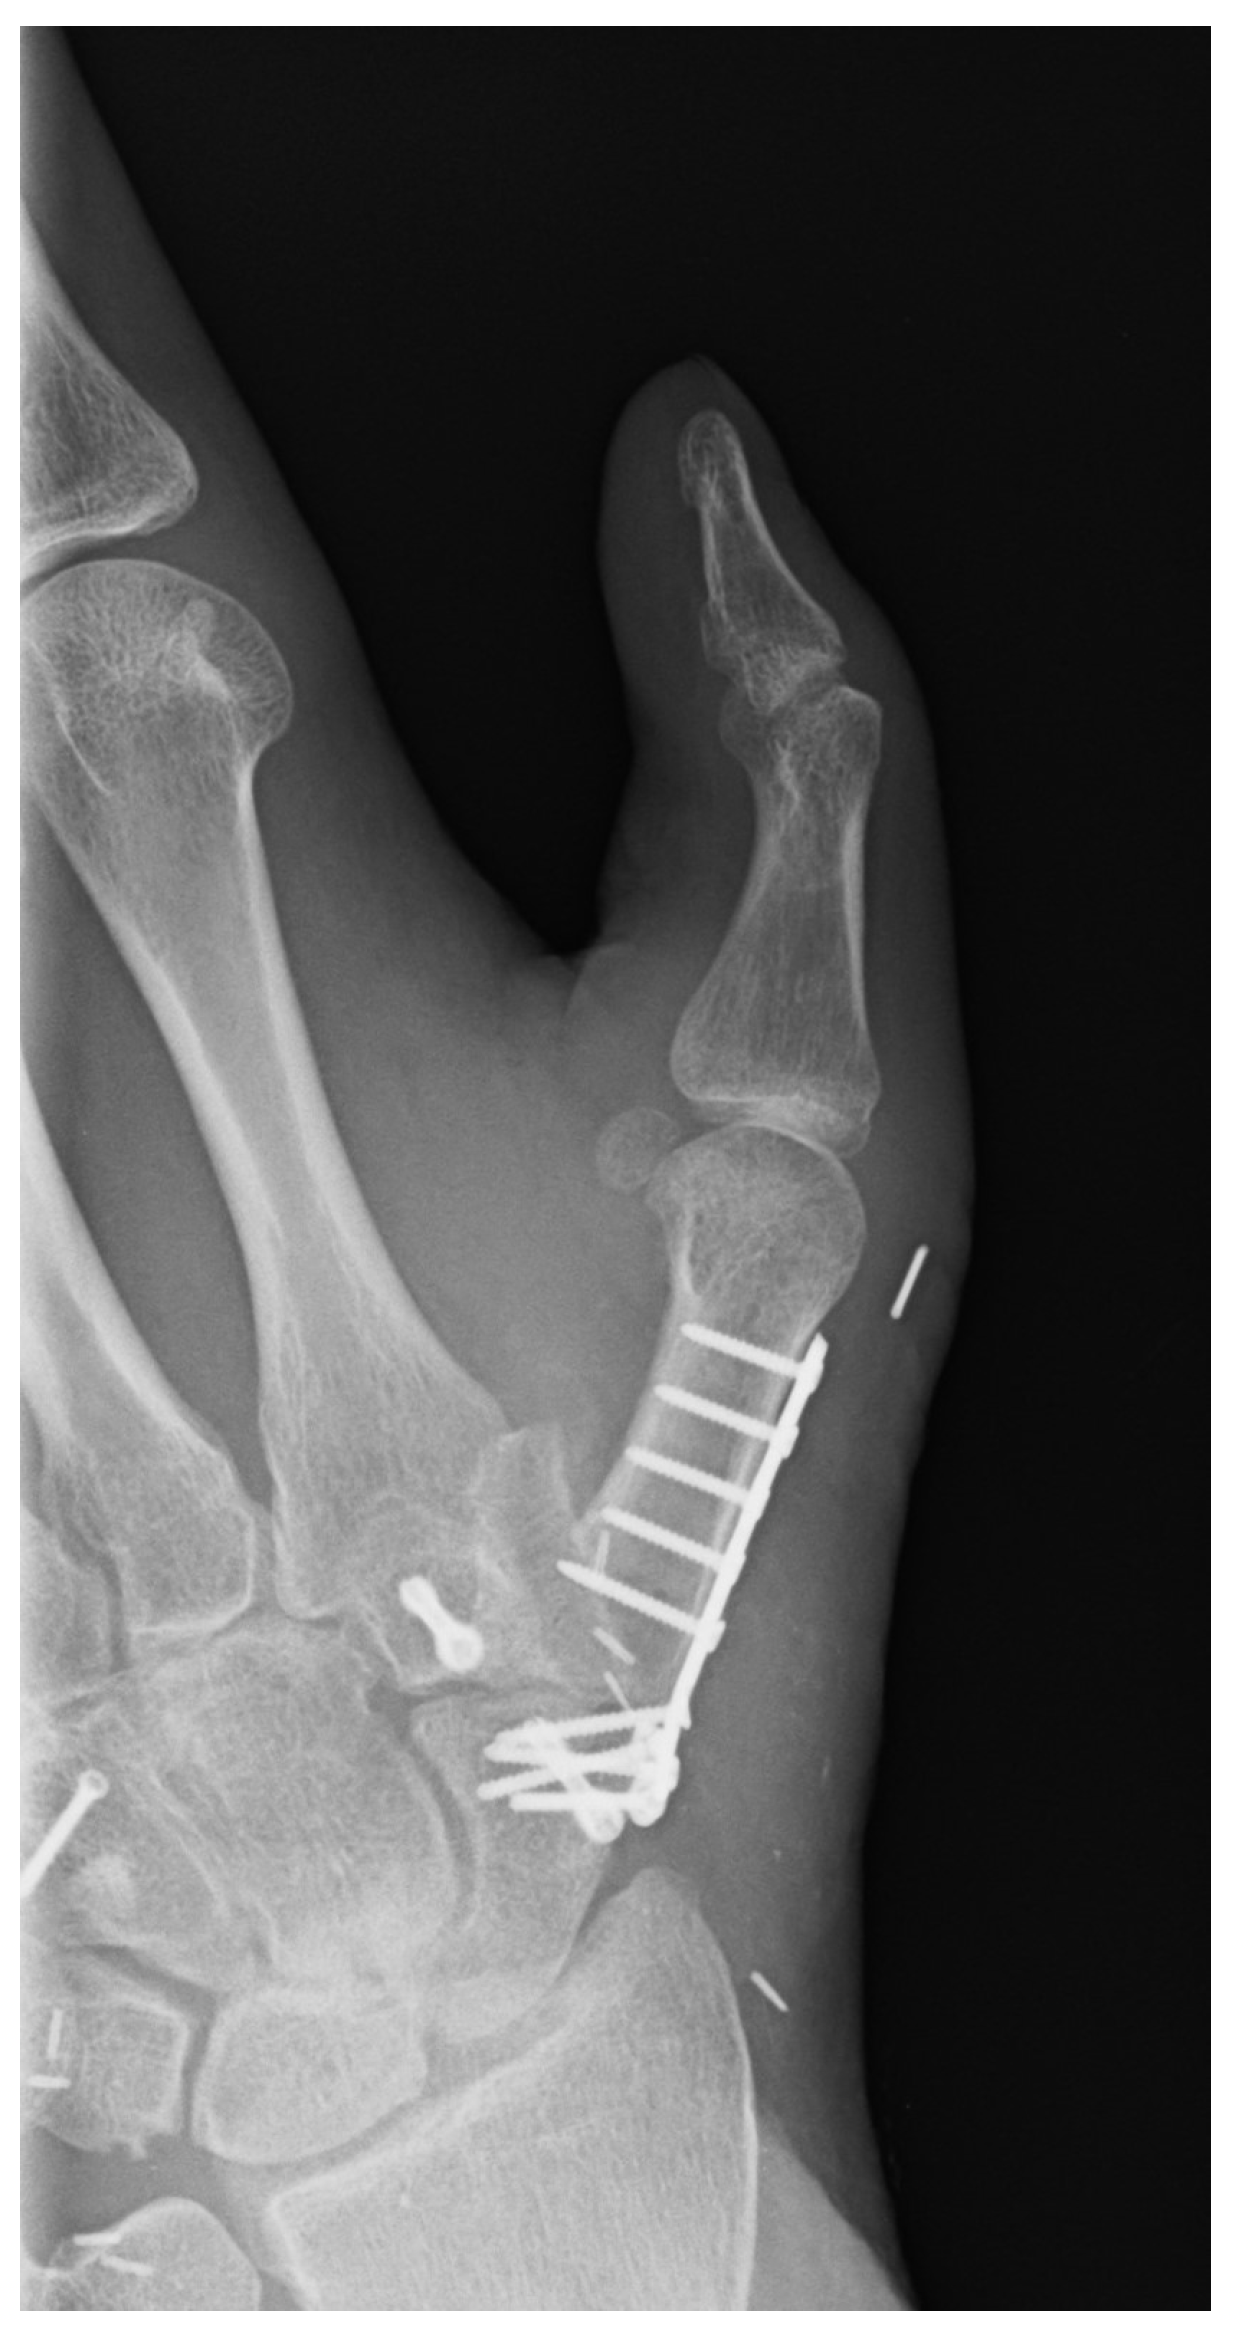

| 1 | 17 | m | Circular saw injury to the dominant left hand with a subtotal amputation of DII–DIV at the level of the MCP joints | Replantation of DIV Amputation of the distal metacarpals DII and DIII, PIP-Joint transfer to DII from the left second toe, MCP endoprosthesis DIII, Free double toe joint transfer to PIP and DIP from the right second toe | Finger-palm distance (FPD) DII–DV 0–0–1–0 cm Fingernail table distance (FNTD) DII–DV 0–0–0–0 cm Kapanji 10/10. DII: MCP 0–0–80°, PIP 0–0–100°, DIP 0–0–80°; DIII: MCP 0–0–80°, PIP 0–0–100°, DIP 0–0–50°; DIV: MCP 0–10–90°, PIP 0–0–90°, DIP 0–0–10°; DV: MCP 0–0–90°, PIP 0–0–100°, DIP 0–0–90°. | The two-point discrimination reached 4–6 mm in all fingers. | Pinch left 7 kg, right 10 kg. Force left 8 kg, right 18 kg. |

| 2 | 45 | m | Amputation of the left lower leg because of trauma caused by a steel beam | Initial replantation, Free latissimus dorsi flap, Free ALT flap for ventral defect arthrodesis OSG with vascularized iliac crest | Full weight bearing possible. No ROM OSG because of arthrodesis. | Improvement in sensitivity in the sole of the foot, as well as deep sensitivity in the area of the flap | - |